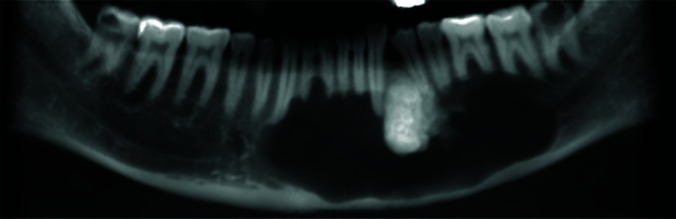

Hybrid lesions of jaws are rare entities defined as two different lesions co-occurring in the same location, with identical histopathological origin. Ameloblastoma, calcifying cystic odontogenic tumor and odontoma are among the most common lesions that have been reported to combine with other lesions. In this study, a hybrid lesion of odontogenic keratocyst (OKC) and odontoma in the mandible of a forty-five years old male reported. Additional to the rarity of this hybrid lesion, the present case had unique radiologic features, including atypical location and extension of the lesion and profound knife-edge root resorption of the teeth in the area, which was not a common feature for any of the two lesions. The surgical procedure was marsupialization to reduce the size of the lesion. As a result of the surgery, the healing of the surgical wound was uneventful. In addition, careful follow-up for the patient was conducted, which had no recurrence till now (after 15 months).